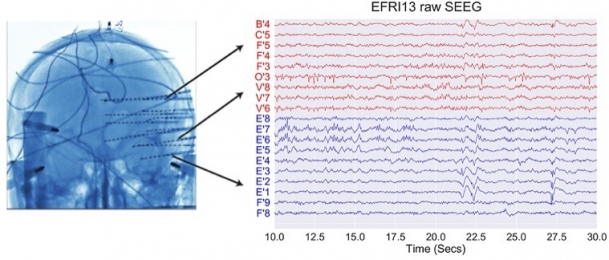

Our research leverages on the rare opportunity of measuring brain activity intracranially in patients affected by pharmaco-resistant epilepsy. In pharmaco-resistant epilepsy patients, neurologists use intracranial electroencephalography (iEEG) to delineate the epileptogenic focus, when non-invasive scalp EEG and other techniques have been insufficient to localize it. iEEG is recorded with intracranial electrodes and it has higher spatial resolution and higher signal-to-noise ratio than scalp EEG.

iEEG is generally more used in mesial temporal lobe epilepsy. Therefore, the clinical intracranial macroelectrodes often record electrophysiology signals from the hippocampus, the entorhinal cortex and the amygdala, which are very important for cognitive processes such as memory. However, other areas, such as the frontal cortex, are also not uncommon implantation targets.

| image credits [1] | image credits [2] |

2. © Greene et al., 2021. Reproduced according to the terms of Creative Commons Attribution License. Greene, Patrick, Adam Li, Jorge González-Martínez, and Sridevi V. Sarma. 2021. “Classification of Stereo-EEG Contacts in White Matter vs. Gray Matter Using Recorded Activity.” Frontiers in Neurology 11 (January). https://doi.org/10.3389/fneur.2020.605696.